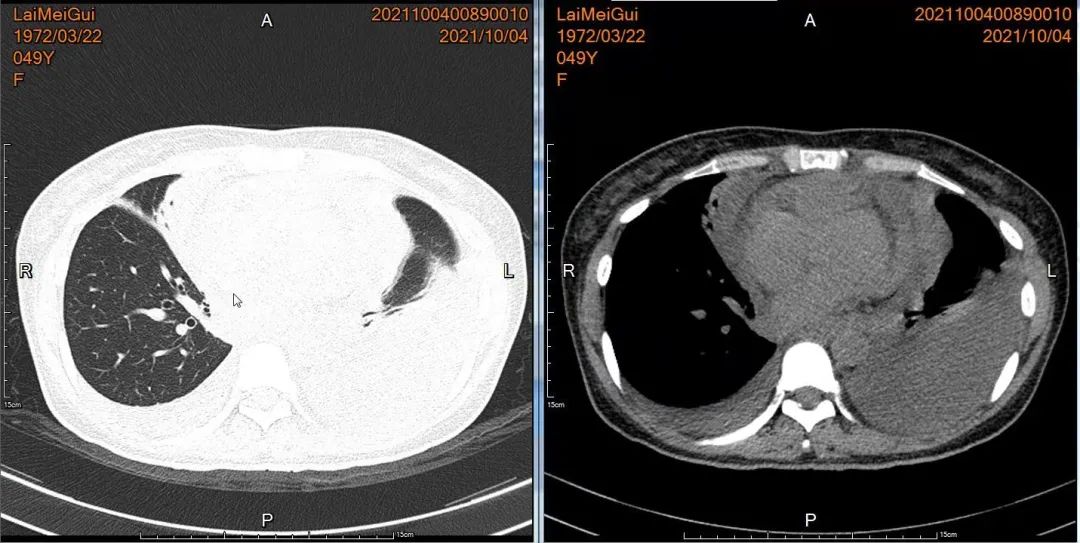

胸部CT双侧胸腔积液,中等量心包积液